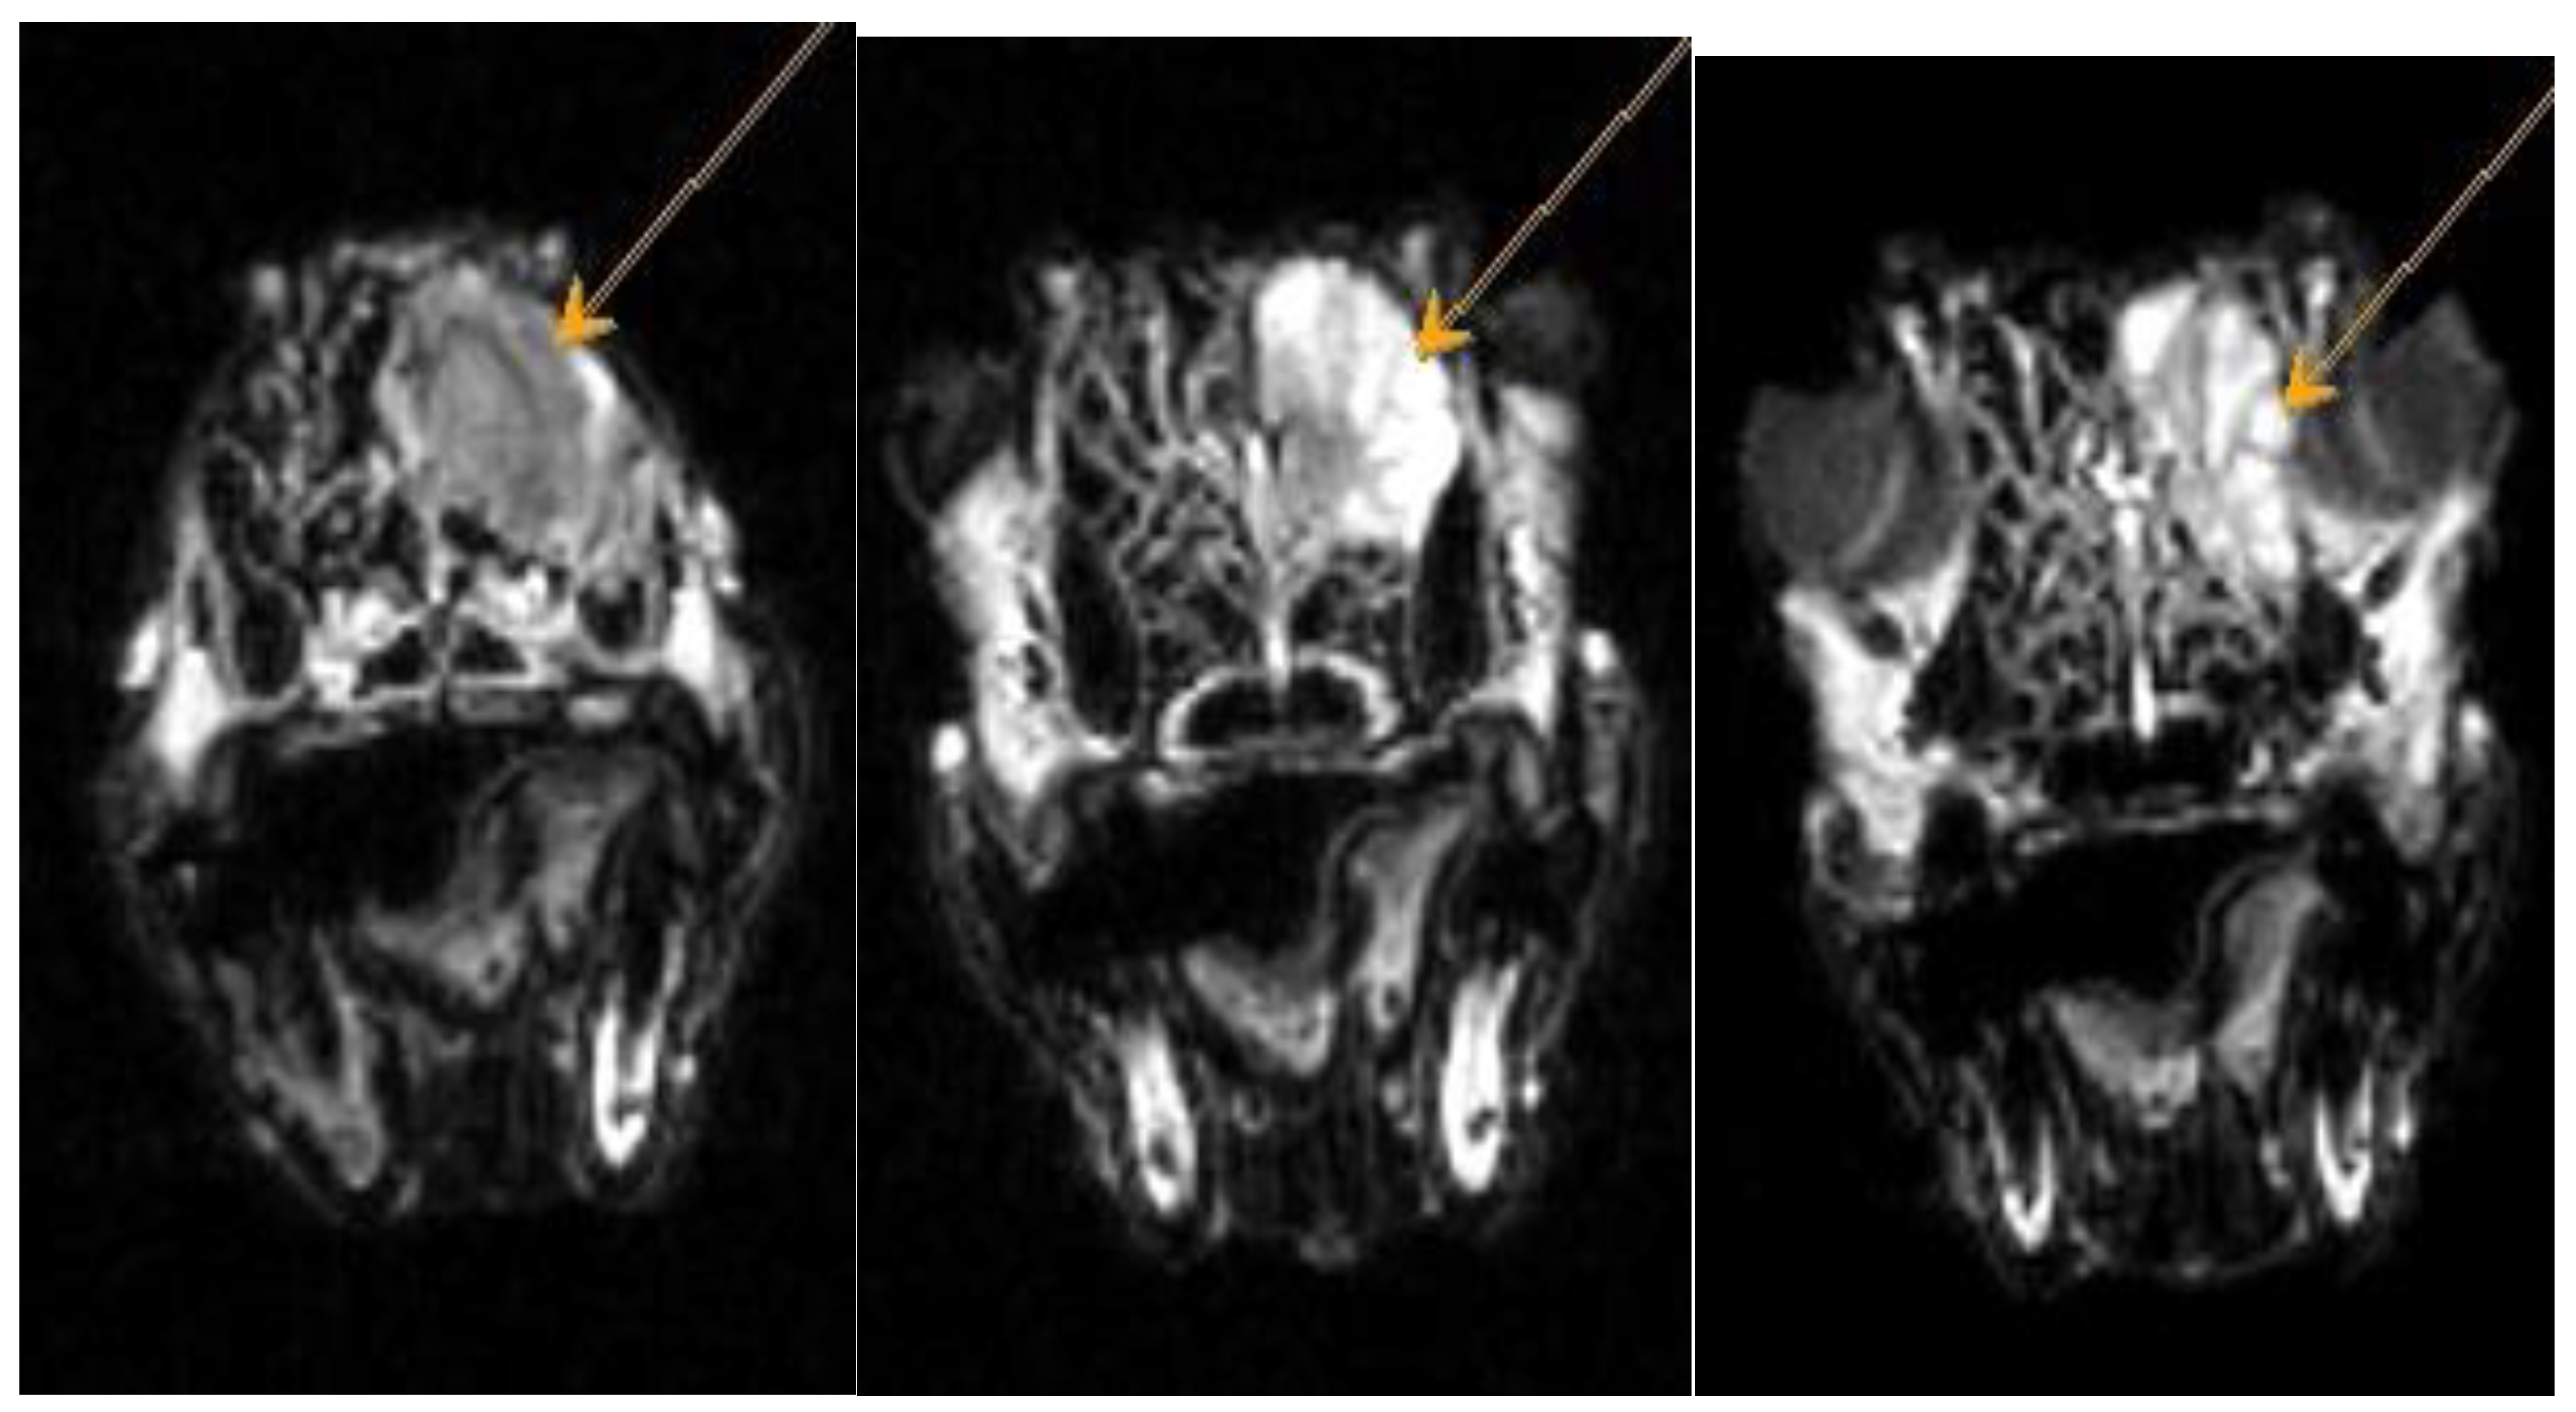

Figure A3. Dachshund dog, 13 years old, 9 kg. FLAIR mode axial plane. Heterogeneous hyperintense signal from the area of the ethmoid bone – neoplasm.

Figure A4. Dachshund dog, 13 years old, 9 kg. T1-VI mode axial plane. Heterogeneous weakly hyperintense signal from the nasal cavity - neoplasm.